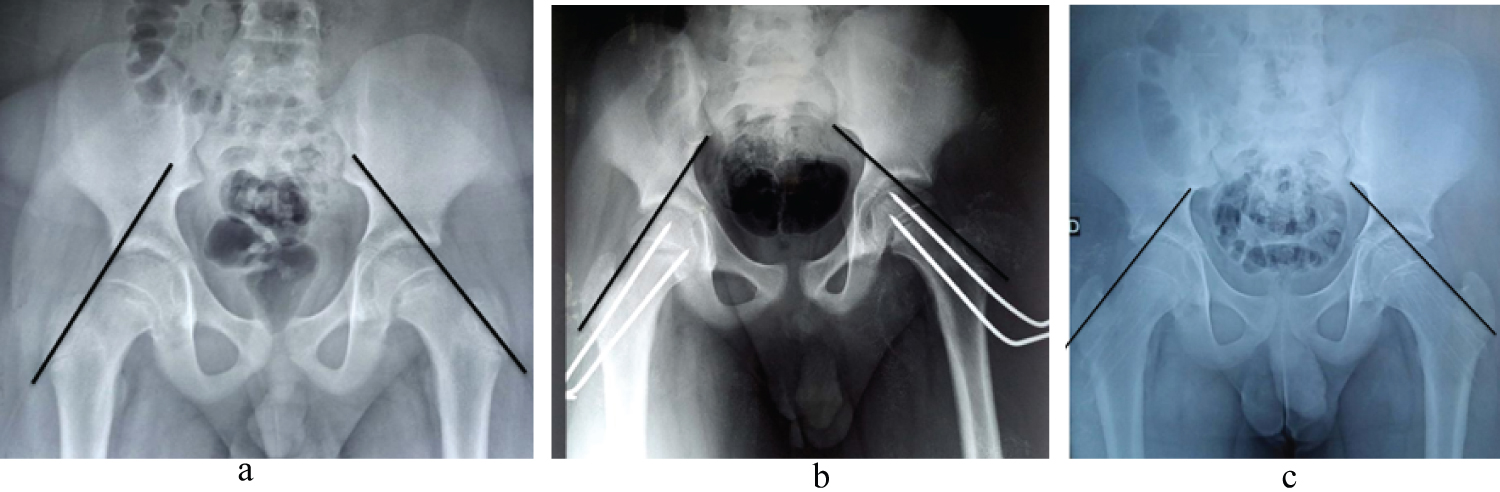

This was a four-year retrospective descriptive study, from January 1, 2017 to December 31, 2020. All patients with upper femoral epiphysiolysis (EFS) treated by simple pinning or percutaneous screw fixation with a postoperative follow-up of at least six (6) months were included. The diagnosis of EFS was established on clinical and paraclinical grounds following a consultation. X-rays of the pelvis and profile enabled us to classify the degree of slippage according to Carlioz. Follow-up was clinical and paraclinical, enabling us to assess post-treatment evolution with a view to detecting and treating complications. On each patient's pelvic X-ray, we determined Klein's line (Figure 1), which is the tangent to the upper edge of the neck, no longer passing through the upper edge of the superior ossification nucleus. On the strict profile X-ray, we traced the SOUTHWICH angle (Figure 2).

Figure 1: EFS acute right. View Figure 1

Figure 2: Southwich angle plot. View Figure 2